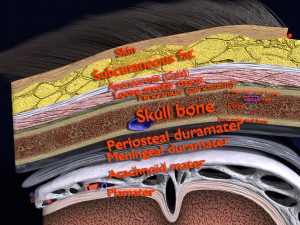

A blend model of brain along with its covering layers (meninges), skull bone and scalp labelled in detail and anatomically precise. The parts depicted are white, gray, pia, arachnoid, dura, bone, skin, fat, aponeurosis, periosteum, falx cerebri and more.

The material is high resolution image textures and normal maps based on non overlapping UVs. The texture and normal maps are packed with the blend file itself.